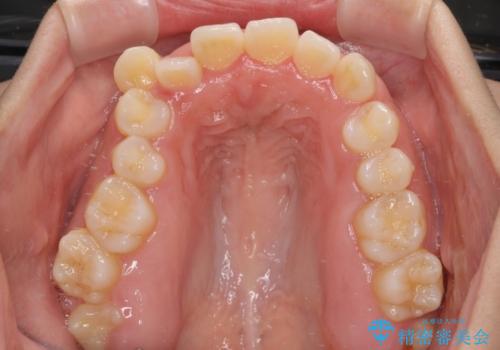

上顎歯列が下顎の歯列に対して狭小であり、一部下顎の奥歯が上顎よりも外側に位置している状態でした。

上顎の急速拡大装置を使用して上顎骨を側方に拡大することで上顎歯列を拡大し、下顎歯列も拡大できるようにすることで、歯列を整えることとしました。

歯列矯正では基本的に骨格を改善することはできませんが、急速拡大装置(MARPE)を使用することで上顎骨を側方に拡大させることができ、咬合状態を大きく改善することができます。